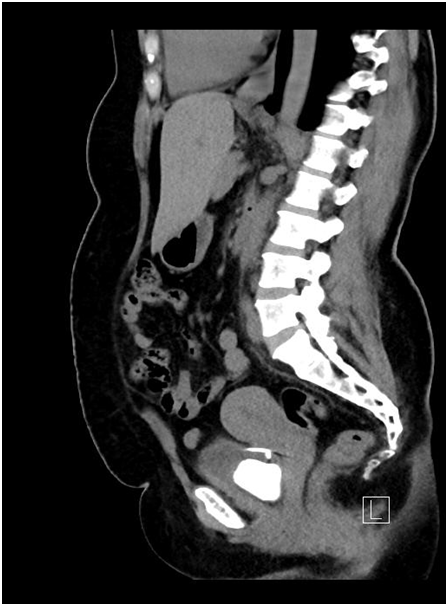

On initial evaluation with ultrasound (Figure 1) revealed a vesical calculus. On further evaluation with X-ray KUB (Figure 2) and CT Scan (Figure 3) (Figure 4) showed large laminated vesical calculus and Copper T seen outside the uterus with horizontal portion in the vesicouterine pouch, long vertical portion seen protruding into the urinary bladder lumen through the posterior wall partly encased in the vesical calculus.

Figure 2 X-ray KUB.